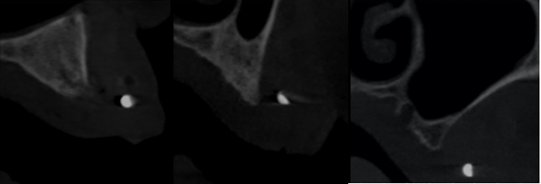

Figure 10: Paraaxial cuts of region 22-24-28.

A well-defined unilocular radiolucent image in maxillary anterior region: Nasopalatine duct cyst (Figure 11).

Figure 11: Nasopalatine duct cyst.